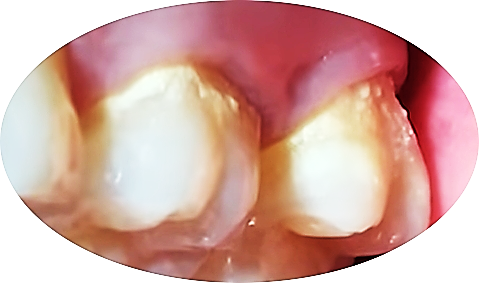

스케일링하면 치아에 금이 가거나 패이지 않을까 걱정하는 분이 많으신데요. 절대로 그런 일은 발생하지 않습니다.

스케일링 후 1~2주 정도 시릴 수 있는데 이것은 극히 정상적인 반응입니다.

스케일링 후에 치아 사이 공간 ‘블랙 트라이앵글’이 보이기도 하는데 이것은 그동안 잇몸병이 진행되어 부었던 것이 가라앉으면서 생긴 흔적입니다.

스케일링 부작용으로 잘못 오해하시는 분들이 계십니다.